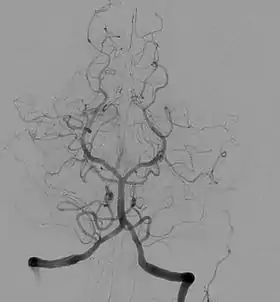

Angiography

Angiography is the use of fluoroscopy to view the cardiovascular system. An iodine-based contrast is injected into the bloodstream and watched as it travels around. Since liquid blood and the vessels are not very dense, a contrast with high density (like the large iodine atoms) is used to view the vessels under X-ray. Angiography is used to find aneurysms, leaks, blockages (thromboses), new vessel growth, and placement of catheters and stents. Balloon angioplasty is often done with angiography.